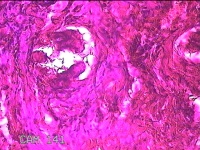

下唇肿物

性别

男

年龄

34岁

临床诊断

唇粘液囊肿

一般病史

下唇肿物2周。

标本名称

大体所见

灰白暗红色肿物0.7x0.5x0.3cm一个,表面光滑。